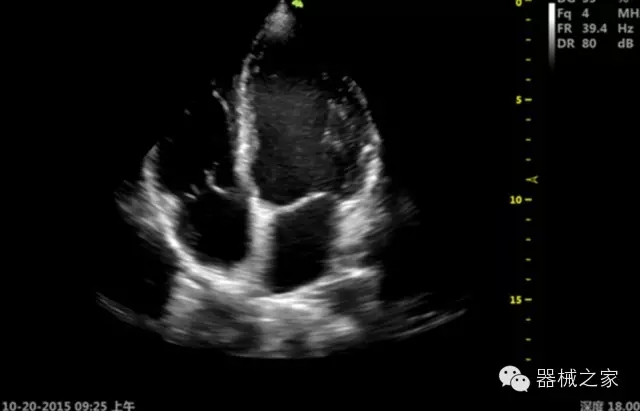

臨床圖片賞析

·飛依諾特有心臟純凈波探頭提供更好的穿透力和彩色敏感度,以及結(jié)合TView梯形拓展改善困難病人深部組織成像;

·獨有RF敏感血流使得心臟血流完美呈現(xiàn);